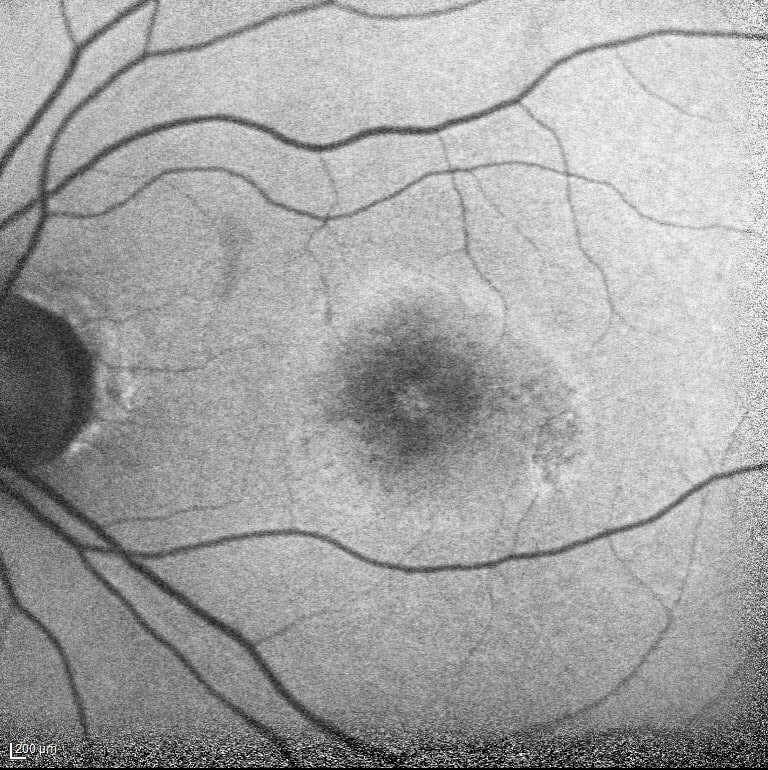

光干渉断層血管撮影 Optical Coherence Tomography Angiography(OCTA)

OCTAでは、網目状新生血管がみられる。

Cross Sectional-OCTA(CS-OCTA BモードOCTA画像)ではdouble-layer signを示す隆起したRPE下に血流信号(赤色)がみられる。漿液性網膜剥離を伴っており活動性のある1型CNVと診断した。